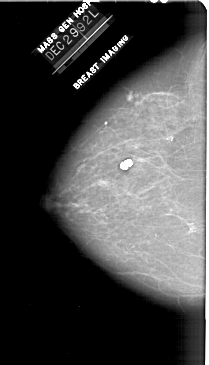

A_1910_1.RIGHT_MLO

RIGHT_MLO LINES 5596 PIXELS_PER_LINE 3226 BITS_PER_PIXEL 12 RESOLUTION 43.5 OVERLAY

FILE: A_1910_1.RIGHT_MLO.OVERLAY

TOTAL_ABNORMALITIES 1

ABNORMALITY 1

LESION_TYPE CALCIFICATION TYPE PLEOMORPHIC DISTRIBUTION CLUSTERED

ASSESSMENT 4

SUBTLETY 3

PATHOLOGY BENIGN